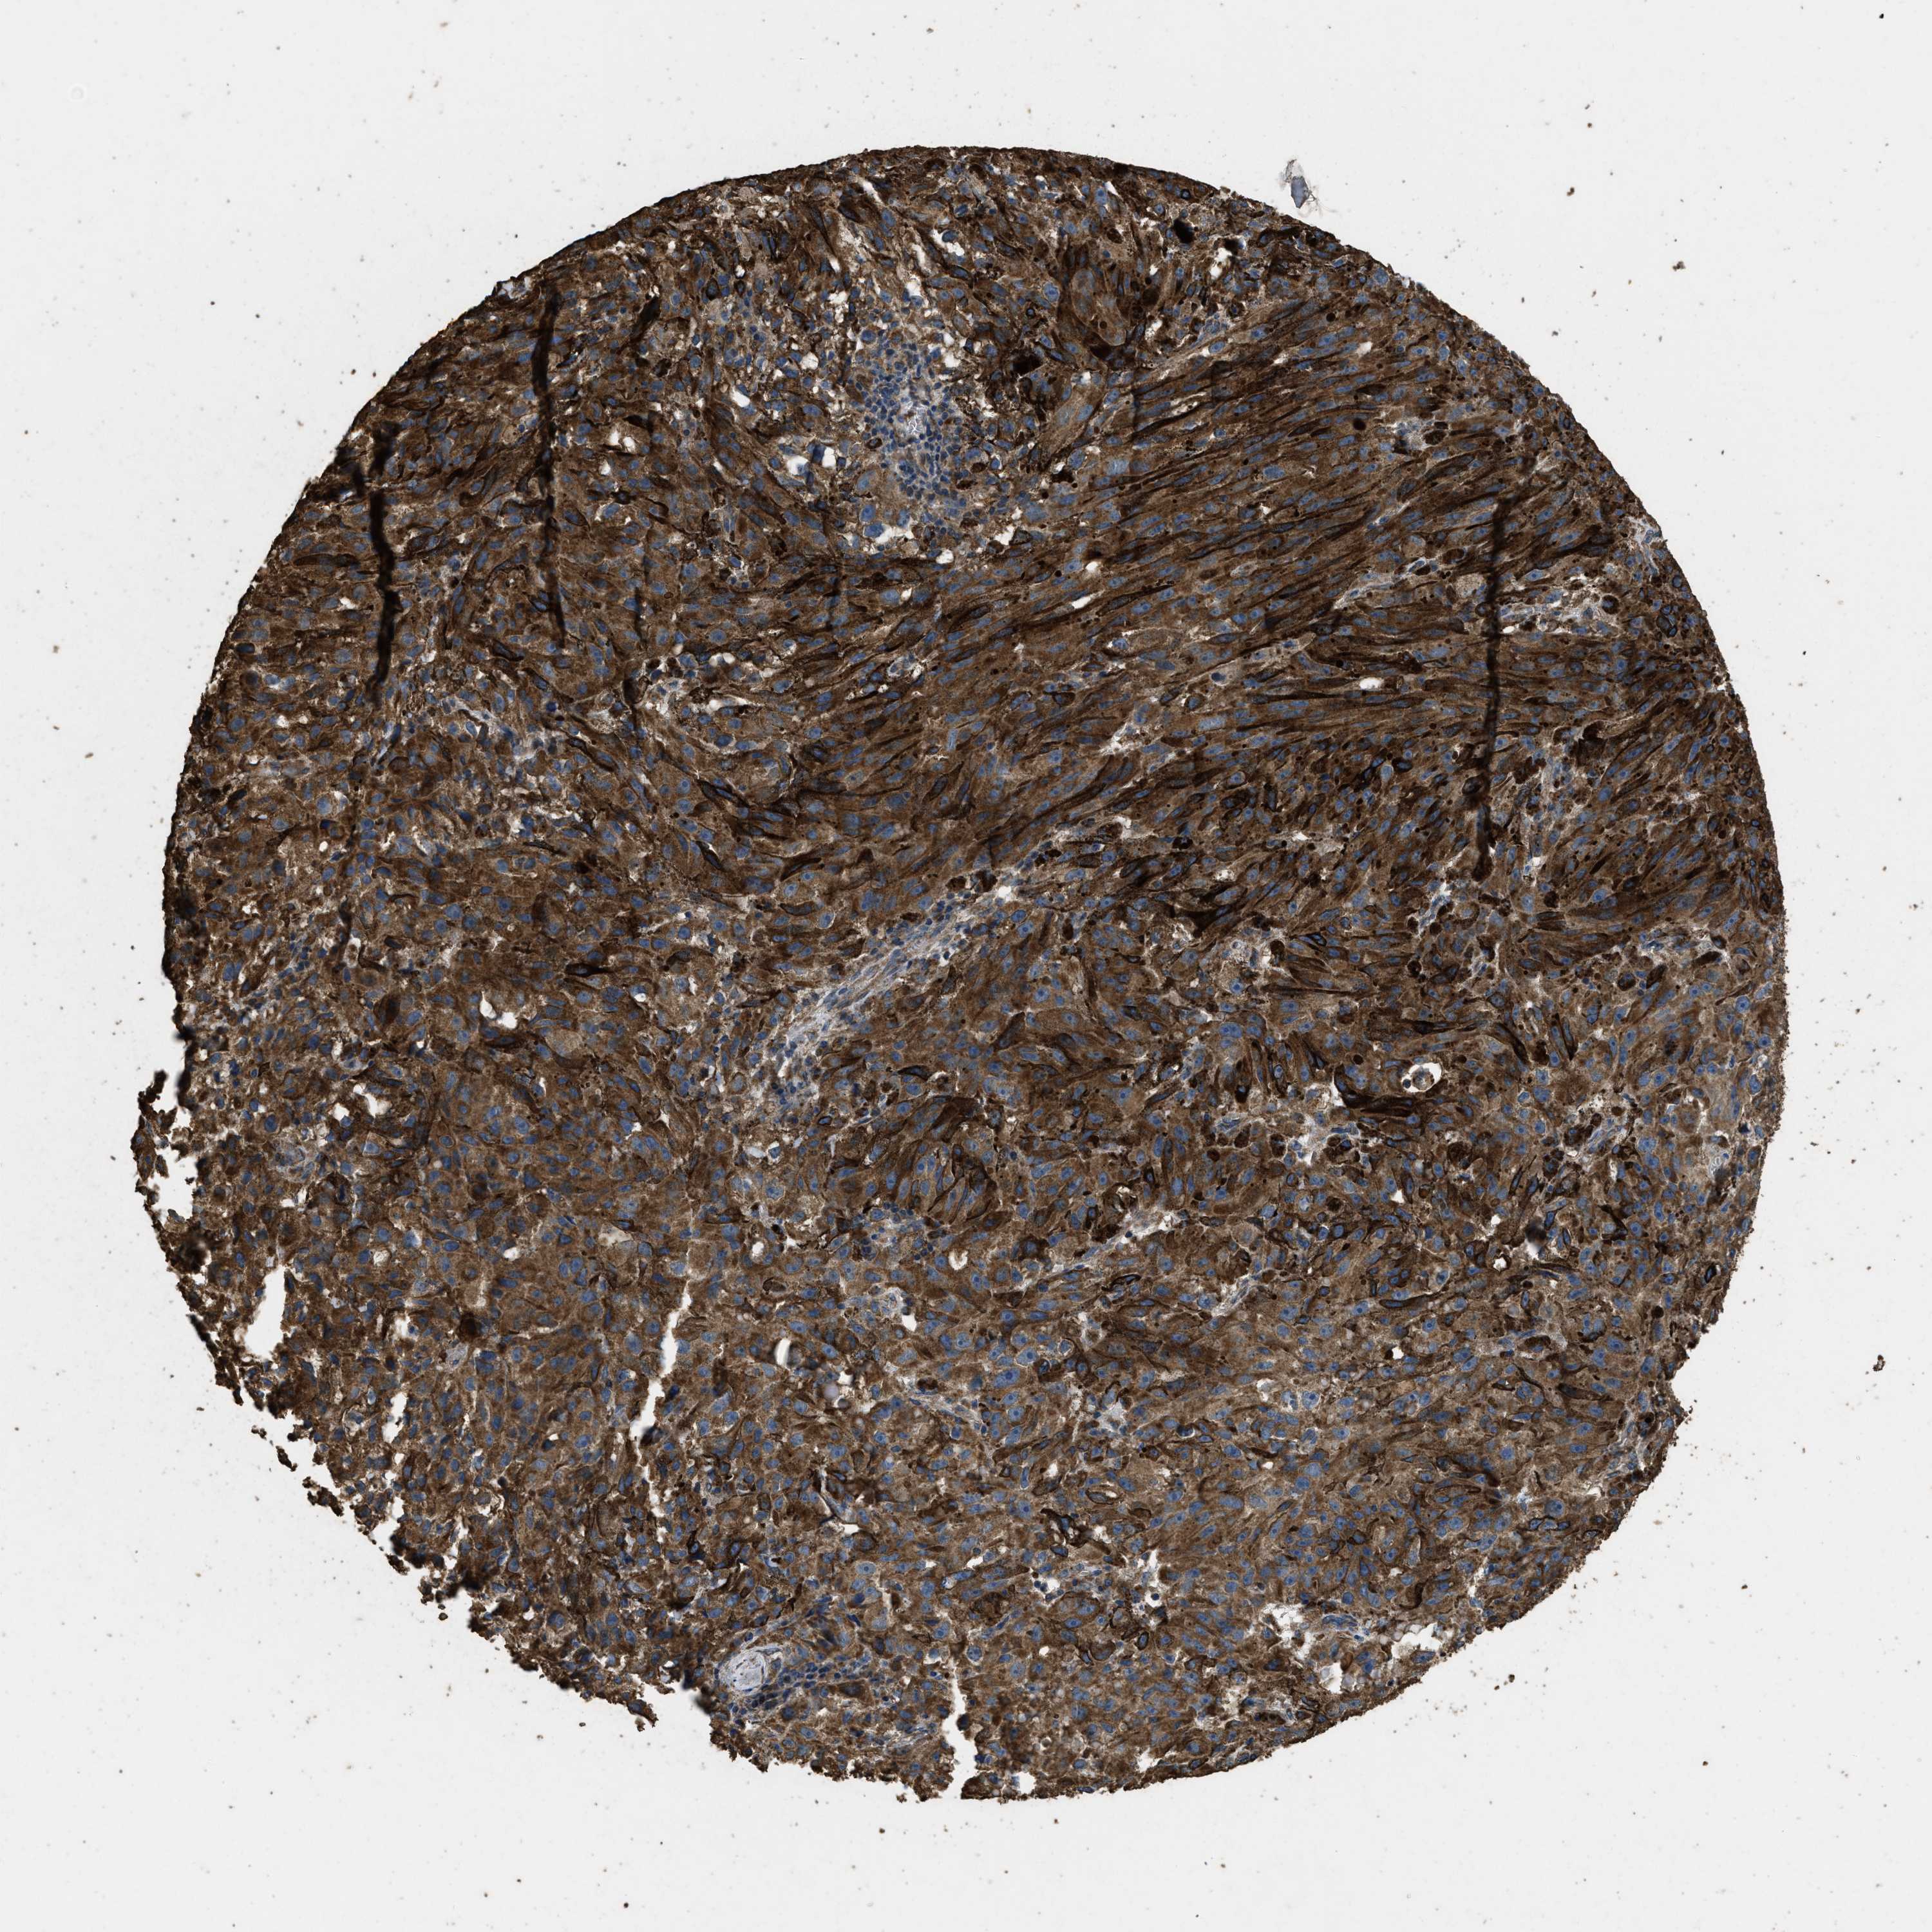

MELANOMA - Protein expressioni

A mouse-over function shows sample information and annotation data. Click on an image to view it in a full screen mode. Samples can be filtered based on level of antibody staining by selecting one or several of the following categories: high, medium, low and not detected. The assay and annotation is described here.

Note that samples used for immunohistochemistry by the Human Protein Atlas do not correspond to samples in the TCGA dataset.

Antibody stainingi

Antibody staining in the annotated cell types in the current human tissue is reported as not detected, low, medium, or high, based on conventional immunohistochemistry profiling in selected tissues. This score is based on the combination of the staining intensity and fraction of stained cells.

Each image is clickable and will lead to virtual microscopy that enables deeper exploration of all samples and also displays staining intensity scores, fraction scores and subcellular localization as well as patient and tissue information for each sample.

Antibody CAB017847

Staining

High

Medium

Low

Not detected

Intensity

Strong

Moderate

Weak

Negative

Quantity

>75%

75%-25%

<25%

None

Location

Nuclear

Cytoplasmic/membranous

Cytoplasmic/membranous,nuclear

Malignant melanoma, NOS

Malignant melanoma, Metastatic site